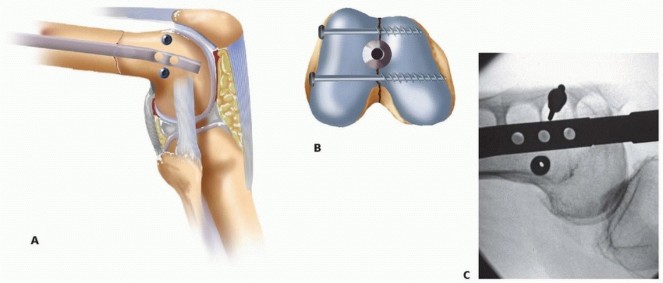

FIG 6 • A. Diagram of lateral aspect of distal femur, with potential sites for intra-articular screw fixation out of the path of the retrograde femoral nail identified. B. Diagram of distal femur end on, with potential sites for intra-articular screw fixation out of the path of the retrograde femoral nail identified. C. Intraoperative lateral radiograph of a supracondylar, intracondylar (C1) distal femur fracture with intra-articular screw fixation and retrograde nail in place. Consideration for retrograde femoral nailing can be given to simple transverse articular fracture patterns (C-1 and C-2 subgroups). This should be performed with an open medial or lateral parapatellar approach to the knee in lieu of a percutaneous approach. Articular reduction must first be obtained and then maintained with bicortical screw fixation placed outside of the planned path for the retrograde nail ( FIG 6). Partial articular fractures (all B subgroups) and complex articular fractures (C-3 subgroups) should not be considered for retrograde femoral nailing. Patients with osteoporotic distal fractures may be best treated with some of the newer fixed-angle plate devices, owing to concerns of distal interlocking screw purchase. Alternatively, nails designed with multiaxial screws or the use of supplemental blocking screws may help with augmenting fixation. ## Contraindications Preoperative knee stiffness preventing 40 to 60 degrees of flexion Active knee sepsis Grossly contaminated soft tissue wounds about the knee remain a contraindication but recent literature has shown that retrograde nailing of open fractures does not increase the incidence of postoperative knee sepsis. 22 Skeletally immature patients ## Preoperative Planning AP and lateral radiographs are used to measure the diameter of the femoral canal isthmus and thus determine the approximate nail diameter. Most intramedullary nail systems come in diameters ranging from 10 to 13 mm.*

FIG 6 • A. Diagram of lateral aspect of distal femur, with potential sites for intra-articular screw fixation out of the path of the retrograde femoral nail identified. B. Diagram of distal femur end on, with potential sites for intra-articular screw fixation out of the path of the retrograde femoral nail identified. C. Intraoperative lateral radiograph of a supracondylar, intracondylar (C1) distal femur fracture with intra-articular screw fixation and retrograde nail in place. Consideration for retrograde femoral nailing can be given to simple transverse articular fracture patterns (C-1 and C-2 subgroups). This should be performed with an open medial or lateral parapatellar approach to the knee in lieu of a percutaneous approach. Articular reduction must first be obtained and then maintained with bicortical screw fixation placed outside of the planned path for the retrograde nail ( FIG 6). Partial articular fractures (all B subgroups) and complex articular fractures (C-3 subgroups) should not be considered for retrograde femoral nailing. Patients with osteoporotic distal fractures may be best treated with some of the newer fixed-angle plate devices, owing to concerns of distal interlocking screw purchase. Alternatively, nails designed with multiaxial screws or the use of supplemental blocking screws may help with augmenting fixation. ## Contraindications Preoperative knee stiffness preventing 40 to 60 degrees of flexion Active knee sepsis Grossly contaminated soft tissue wounds about the knee remain a contraindication but recent literature has shown that retrograde nailing of open fractures does not increase the incidence of postoperative knee sepsis. 22 Skeletally immature patients ## Preoperative Planning AP and lateral radiographs are used to measure the diameter of the femoral canal isthmus and thus determine the approximate nail diameter. Most intramedullary nail systems come in diameters ranging from 10 to 13 mm.*